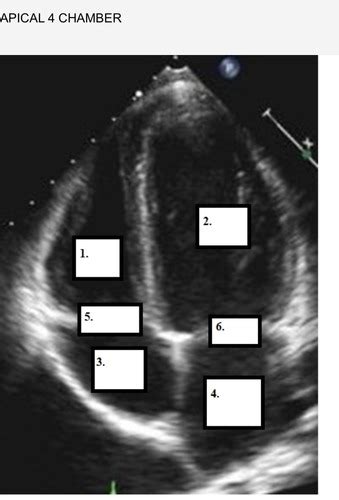

So, why is the apical view echo probe position so darn important? Well, imagine trying to understand how a car engine works by only looking at it from the side. You’d miss a ton of crucial details about how the pistons move, how the valves open and close, and the overall efficiency of the system. The apical view is kind of like that – it offers a unique perspective that other views just can’t replicate. When we talk about echocardiography, we’re essentially using sound waves to create moving pictures of the heart. The apical view, typically obtained from the apex of the heart (the pointy bottom part), gives us a fantastic look at all four chambers – the left atrium, left ventricle, right atrium, and right ventricle – in a way that highlights their size, shape, and most importantly, their function . We can directly visualize the systolic function (how well the heart is squeezing) and diastolic function (how well it’s relaxing) of the left ventricle, which is absolutely critical for diagnosing and managing conditions like heart failure, cardiomyopathies, and valvular heart disease. Furthermore, the apical view is gold standard for evaluating the mitral valve, our heart’s “inflow valve” for the left ventricle. We can see its leaflets move, check for regurgitation (leakage), or stenosis (narrowing). The tricuspid valve, on the other side, is also well-visualized in certain apical projections. Think about conditions like mitral valve prolapse or severe aortic stenosis; the apical view is often the first place we confirm the severity and impact of these issues. It also helps us assess for things like pericardial effusions (fluid around the heart) or thrombus (blood clots) within the cardiac chambers. Without mastering the apical view, you’re essentially flying blind in many diagnostic scenarios. It’s the foundation upon which many other diagnostic conclusions are built. So, when you’re aiming for that apical probe position, remember you’re not just trying to get a pretty picture; you’re gathering vital information that directly impacts patient care and clinical decision-making. It allows us to quantify stroke volume, cardiac output, and ejection fraction, which are key metrics for assessing overall heart health. The visual evidence from a well-obtained apical view can be incredibly persuasive and informative for both referring physicians and the patient themselves. It truly is a cornerstone of a complete echocardiographic examination, guys, and worth every bit of effort to perfect.

Alright team, let’s get down to the nitty-gritty of achieving that perfect apical view echo probe position . It might seem intimidating at first, but follow these steps, and you’ll be capturing stellar images in no time. First things first: patient positioning . The patient should ideally be lying on their left side, also known as the left lateral decubitus position. Why the left side, you ask? Because this rolls the heart towards the transducer, bringing the apex closer to the chest wall and minimizing the distance sound waves have to travel through lung tissue, which can scatter ultrasound signals. Ask the patient to bring their left arm up and over their head or rest it on a pillow. This helps to abduct the left arm and open up the intercostal spaces, giving you better access. Now, for the probe selection . Generally, a phased array transducer (the one with the small, curved footprint, often called a “cardiac probe”) is your best bet. Its shape allows it to get between the ribs easily. Now, where do we place the probe? We’re looking for the apical impulse or point of maximal impulse (PMI) , which is usually felt in the 5th or 6th intercostal space at the mid-clavicular line. You might need to palpate the chest to find this spot. Once you’ve found a likely area, apply a good amount of ultrasound gel – don’t be shy with the gel, guys! It’s essential for good sound transmission. Place the probe perpendicular to the chest wall initially. The probe marker (usually a dot or a line) should be pointing towards the patient’s right shoulder or slightly towards the head. Now, here comes the art: manipulating the probe . Start with a standard apical four-chamber view. You’ll want to fan the probe slightly up and down, side to side, and rock it gently to optimize the image. Think of it like gently sweeping the probe across the area. The goal is to see all four chambers clearly: the left atrium, left ventricle, right atrium, and right ventricle. The left ventricle should be the largest chamber, and you should clearly visualize the mitral valve between the left atrium and left ventricle, and the tricuspid valve between the right atrium and right ventricle. Depth and gain adjustments are also critical. You might need to adjust the depth to ensure the entire heart is in the field of view, and the gain controls help to brighten or darken different parts of the image to make structures more visible. Common adjustments include decreasing the depth and increasing the gain as you get closer to the apex. If you’re having trouble seeing the apex clearly, try moving the probe slightly inferiorly and medially. Sometimes, a slight tilt of the transducer can bring the apex into better view. Remember, patience is key! You might need to try a few different spots and angles. The key takeaway here is left lateral decubitus position , finding the PMI, and then gently fanning and tilting the transducer to achieve optimal visualization of all four chambers and the valves. We’re aiming for that iconic image where the left ventricle looks like a bullet pointing towards the transducer. It’s all about finding that sweet spot where the heart is presenting its best profile to the sound waves. Keep practicing these steps, and you’ll master the apical view in no time, I promise! It’s a journey, but a very rewarding one.

Now that we’ve got the basics of positioning down, let’s talk about really optimizing the apical view echo probe position , specifically the apical four-chamber view. This is arguably the most important apical view, and getting it right means you’re well on your way to a diagnostic echocardiogram. When we talk about optimization, we’re aiming for clarity, completeness, and accuracy. First off, probe orientation is key. Remember we placed the marker pointing towards the patient’s right shoulder for the standard view? To optimize, you might need to slightly adjust this. Think of the probe as having two axes: the long axis (up-down) and the short axis (side-to-side) relative to its footprint. Gently rocking the probe from heel to toe (or toe to heel) helps you see different parts of the heart. Fanning the probe up and down, like opening a book, allows you to sweep through the heart and ensure you’re not missing any structures. You’re looking for a symmetrical appearance of the ventricles and atria, with the interventricular septum and the interatrial septum appearing as thin, distinct lines. Mitral valve visualization is paramount here. You want to see both the anterior and posterior leaflets of the mitral valve clearly opening and closing. If one leaflet seems foreshortened or obscured, try adjusting your probe angle slightly. Sometimes, tilting the probe away from the septum can bring the mitral valve into better view. Similarly, for the tricuspid valve , you want to see its leaflets. It might be slightly less prominent than the mitral valve in this view, but its function is just as important. Symmetry and Proportions are your visual cues for a good four-chamber view. The left ventricle should appear larger than the right ventricle. The atria should also be clearly delineated. If the ventricles look unusually shaped or disproportionate, you might be slightly off-axis, and adjustments are needed. Aortic and Pulmonary Artery Visualization are secondary goals in the four-chamber view but can sometimes be glimpsed. You might see a sliver of the aortic outflow tract posterior to the left atrium, and the pulmonary artery may be seen superiorly. If you need to specifically assess these, you’d move to other views, but their partial visualization here can be helpful for orientation. Doppler Integration is where this view really shines for functional assessment. Placing spectral Doppler on the mitral inflow allows you to assess diastolic function (E-wave and A-wave velocities). Color Doppler across the mitral valve helps identify any regurgitation. Similarly, Doppler on the tricuspid inflow and valve can provide information about right heart function and tricuspid regurgitation. Patient Factors also play a role in optimization. If you have significant lung overinflation (common in COPD patients), you might need to try positioning the patient slightly more upright or even on their right side for a brief moment to see if that improves visualization, though the left lateral decubitus is still preferred. Obesity can also make it harder to reach the apex, requiring deeper penetration and potentially lower-frequency transducers. Don’t be afraid to adjust gain and depth settings dynamically. As you fan through the heart, the optimal settings will change. Many modern machines have automatic gain control (AGC) features, but manual adjustments often yield superior results. The ultimate goal of optimization is to obtain a view that is not only anatomically correct but also allows for accurate functional assessment. This means clear visualization of all four chambers, the interatrial and interventricular septa, and all four valves (mitral and tricuspid are best seen here). So, keep fanning, keep rocking, adjust your depth and gain, and don’t be afraid to make small, precise adjustments. You’re aiming for that textbook image, guys! It takes practice, but the payoff in diagnostic accuracy is immense.